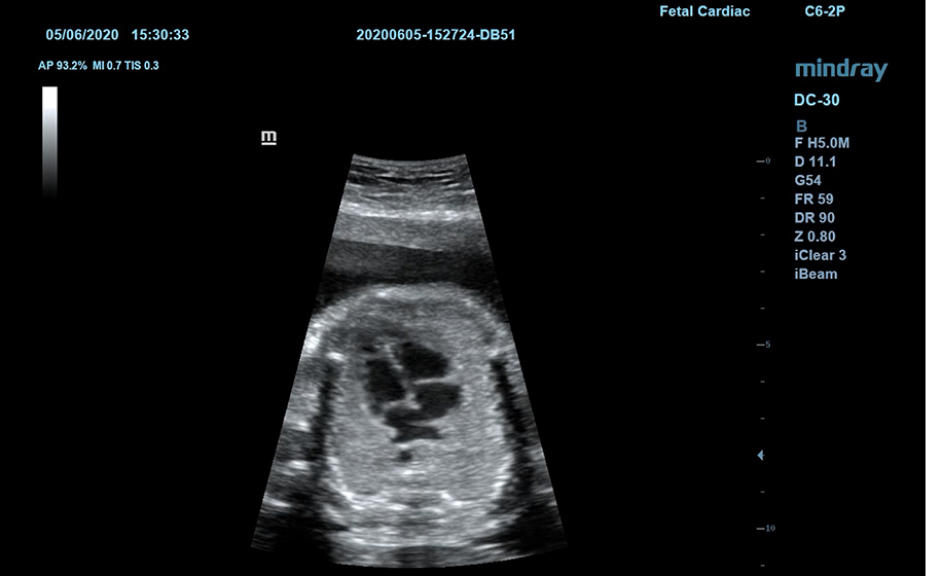

1Широкий выбор плоскостей исследования для конкретных случаев.

Пакеты плоскостей, охватывающие различные области применения: брюшная полость, акушерство и гинекология, щитовидная железа, молочная железа, яички.

Включает различные режимы визуализации.

Анатомические иллюстрации, включающие схемы и УЗИ-изображения.

Боковое отображение стандартной эхограммы, обеспечивающее визуальное наведение на изучаемую область.

Стандартные эхоизображения

3

Сравнение результатов сканирования в реальном времени для справки.